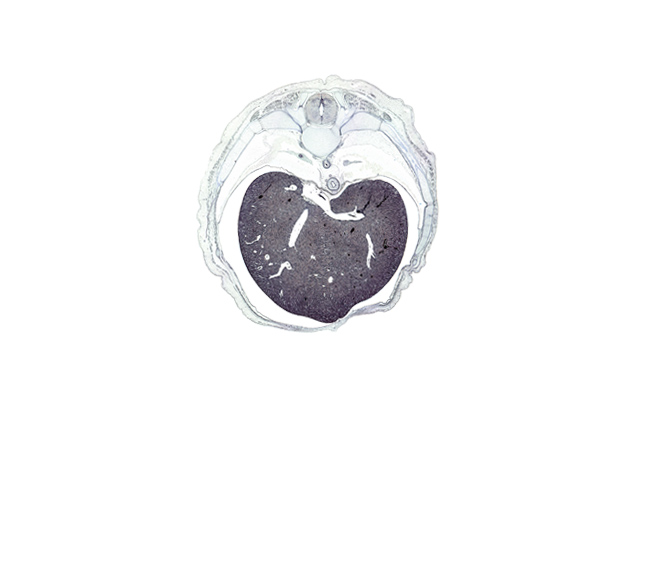

T-8 / T-9 interganglion region, caudal edge of lower lobe of left lung, efferent hepatic vein, efferent hepatic veins, iliocostalis muscle, inferior vena cava, latissimus dorsi muscle, left lobe of liver, longissimus muscle, lower lobe of right lung, multifidus muscle, pedicle of T-8 vertebra, peritoneal cavity, rectus abdominis muscle, rib 10, rib 9, right lobe of liver, spinalis muscle, transverse process of T-8 vertebra

Boyd Embryo #H983   |   Location: 134-1-2

Keywords: T-8 / T-9 interganglion region, caudal edge of lower lobe of left lung, efferent hepatic vein, efferent hepatic veins, iliocostalis muscle, inferior vena cava, latissimus dorsi muscle, left lobe of liver, longissimus muscle, lower lobe of right lung, multifidus muscle, pedicle of T-8 vertebra, peritoneal cavity, rectus abdominis muscle, rib 10, rib 9, right lobe of liver, spinalis muscle, transverse process of T-8 vertebra